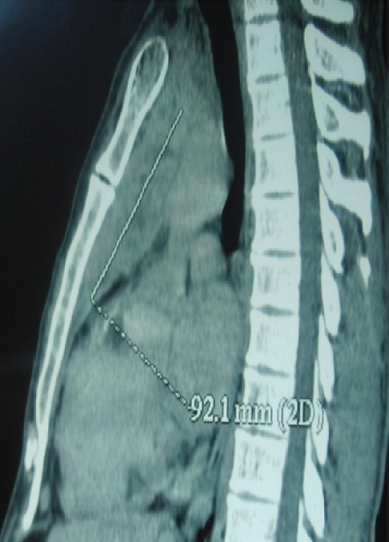

La dermatomyosite amyopathique est une entité rare caractérisée par des lésions cutanées suggestives de dermatomyosite sans atteinte musculaire. Dans les formes paranéoplasiques qui sont rares, le pronostic dépend du type et de la réponse thérapeutique de la tumeur associée. L'association à un carcinome thymique est exceptionnelle. Un patient âgé de 50 ans a été hospitalisé pour exploration d'un érythème du visage et une dyspnée récente. L'examen physique a révélé un érythème héliotrope du visage, des papules de Gottron en regard des articulations interphalangiennes et un érythème douloureux péri-unguéal. Le reste de l'examen était sans particularités. L'examen biologique a montré un syndrome inflammatoire. Le dosage des enzymes musculaires était normal. L'examen immunologique était négatif. L'électromyogramme était sans anomalies. Une biopsie musculaire a montré des fibres musculaires striées normales. Le diagnostic de dermatomyosite amyopathique a été retenu. Dans le cadre de la recherche d'une tumeur associée (digestive, pulmonaire ou gynécologique), les échographies cervicale, abdominale et pelvienne étaient normales. La fibroscopie digestive haute et la coloscopie n'ont révélé aucune anomalie. La TDM thoraco-abdomino- pelvienne a montré une image médiastinale antérieure hétérogène mesurant 92 mm x 40 mm et se réhaussant de façon intense après injection du produit de contraste . Le patient a été opéré par sternotomie permettant une excision complète de la masse. L'examen anatomopathologique a conclu à un carcinome épidermoïde du thymus. Une chimiothérapie et une radiothérapie centrée sur le sternum ont été instaurées. L'évolution était favorable sans notion de récidive avec un recul de trois ans.